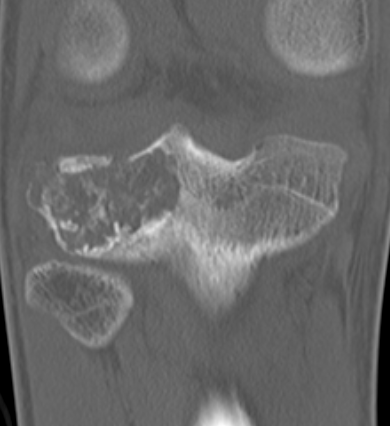

CT

Evaluate articular surface integrity / compromise

Identify chondroid matrix